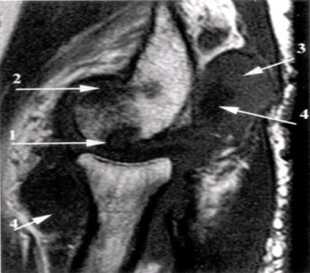

Ревматоидный артрит III стадия выпот в полости сустава (1), грубое эрозирование субхондрального слоя головки плечевой кости (2), фрагментация суставной губы гленоида.

Ревматоидный артрит, II ст. субхондральные жидкостные кисты в эпифизе плечевой кости (1), краевые узуры лучевой кости.

Ревматоидный артрит, III ст. субхондральные эрозии (1) и краевые узуры (2) дистального эпифиза плечевой кости, наличие суставного выпота (3) и массивная гипертрофия синовиальной оболочки (4).